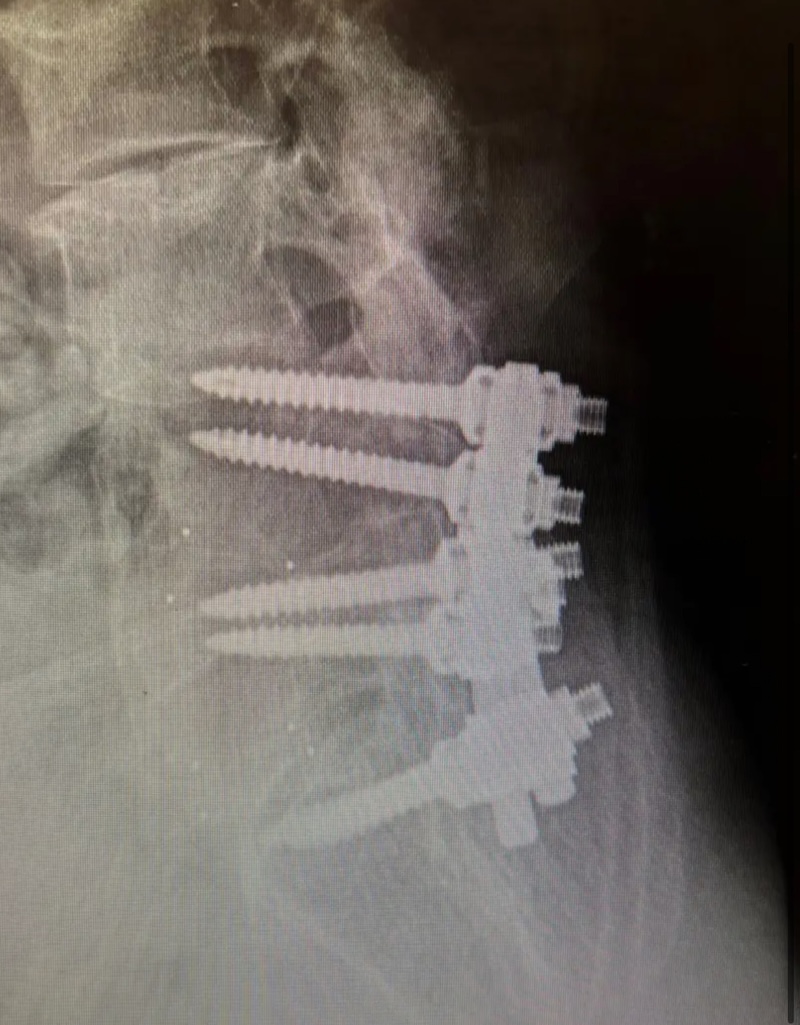

The MONARCH Spine System was originally produced by DePuy and is a titanium thoracolumbar pedicle screw fixation system. It is characterized by the pedicle screw with a polyaxial offset plate.

By Location/Approach: Posterior Thoracic , Posterior Lumbar

By Procedure Type: Thoraco-lumbar-Pelvic Fixation